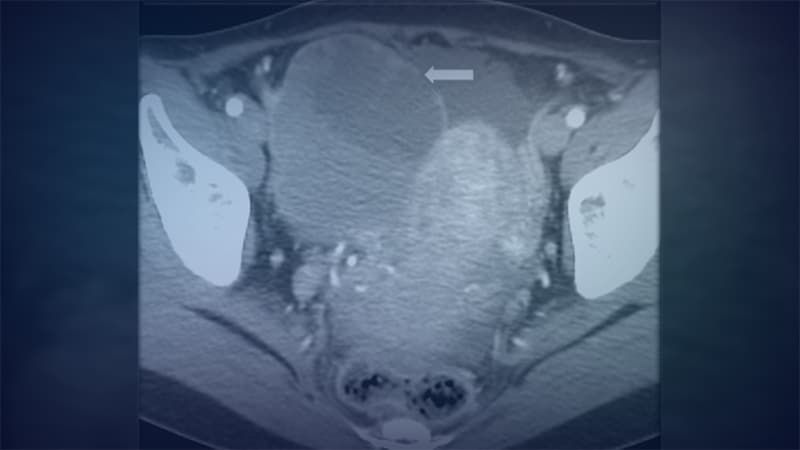

Radiological Case: Schistosoma Bladder Infection